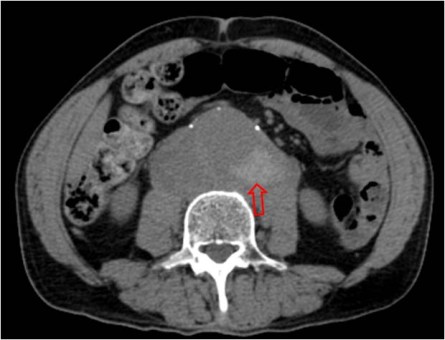

SIGNO DE LA AORTA CAÍDA o SIGNO DEL ABRAZO AÓRTICO

Se trata de otro signo de rotura contenida o inminente. Corresponde a una debilidad de la pared aórtica que provoca que la cara posterior de ésta aparezca como caída sobre el cuerpo vertebral (y ambos psoas, como en este caso -flechas rojas-). También se considera el signo presente cuando es visible un área en la que la pared posterior de la aorta no es identificable como una línea definida.